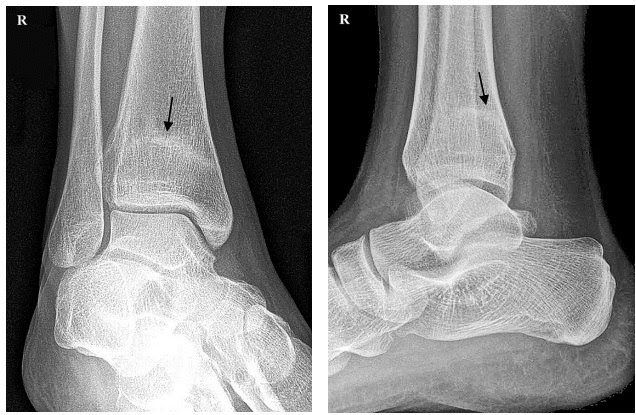

На осмотре заметен отек в виде муфты выше голеностопного сустава, клинические тесты показывают признаки перелома. Рентген подтвердил предварительный диагноз — стресс- перелом большеберцовой кости (стрелка).

Усталостный или стрессовый перелом — результат накопившихся микротравм кости из-за слишком больших физических нагрузок. При этом утомленные мышцы не справляются с ударной нагрузкой и передают ее на кости, вызывая их повреждение.

Стресс-переломы чаще всего возникают на костях ног от стопы до таза. Обычно нет существенных смещений отломков, а часто и явных симптомов. Но при игнорировании травмы могут быть серьезные последствия, вплоть до инвалидизации.